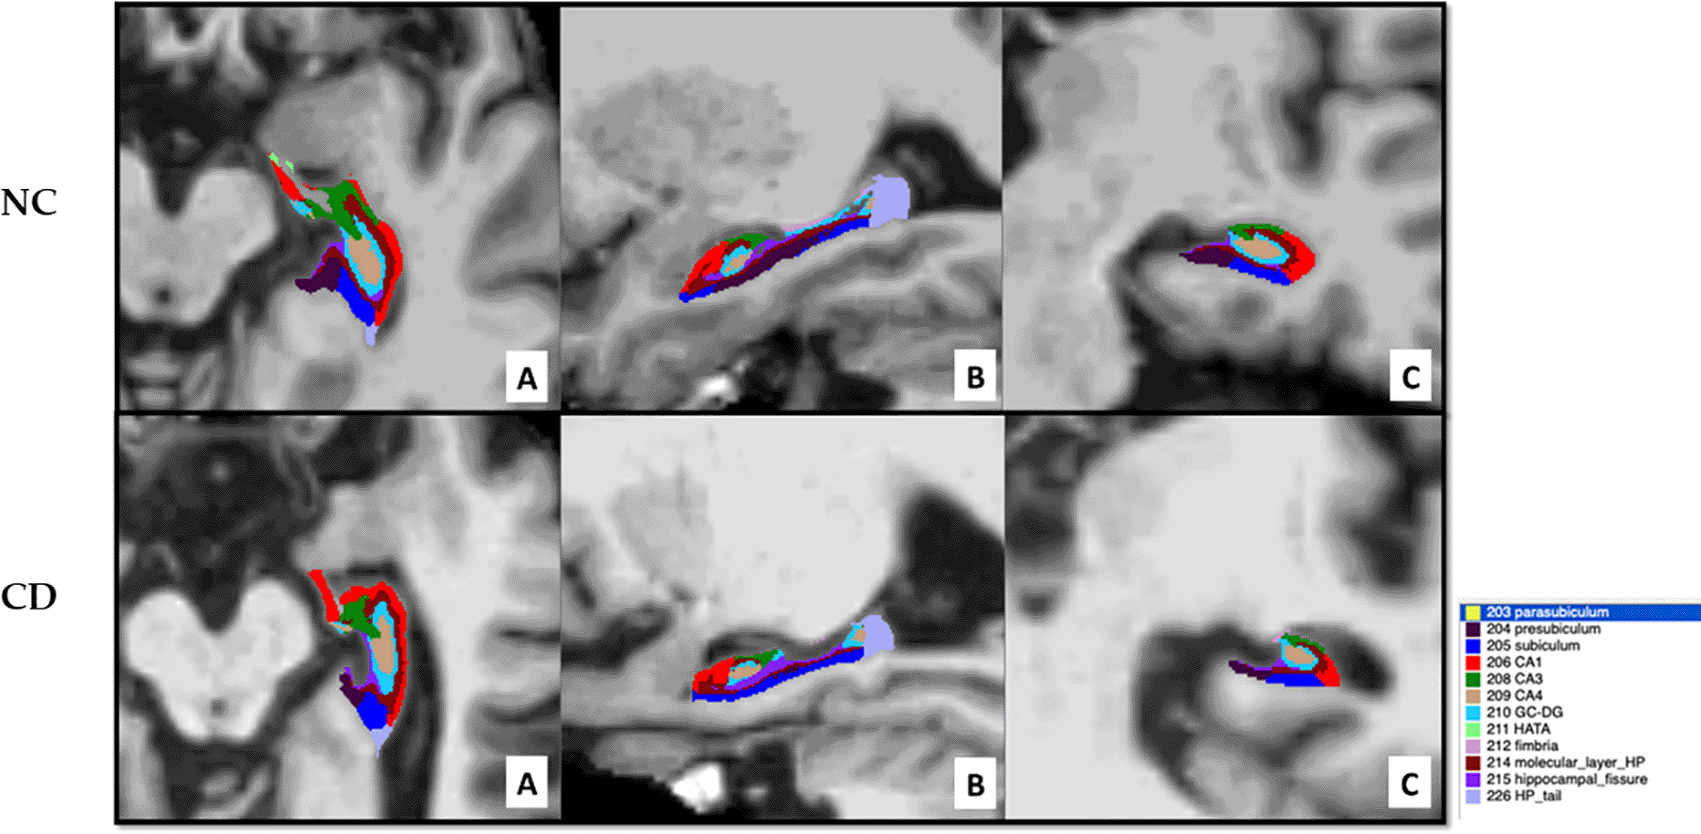

An open source brain image processing software FreeSurfer 6.0 available at https://surfer.nmr.mgh.harvard.edu/was used to perform the automated volumetric analyses for the structural MRI T1-weighted data and/or T2 hippocampal images.21 The FreeSurfer 6.0 pipeline recon - all was run to compute the probabilistic estimated segmented volumes of the left and right whole hippocampus and of the multi-label hippocampal substructures. The hippocampal substructures that are segmented by the software are: hippocampal tail, parasubiculum, presubiculum, subiculum, CA1, CA2 + CA3, CA4, hippocampus–amygdala transition area (HATA), granule cell layer of dentate gyrus (GC-DG), molecular layer, fimbria and hippocampal fissure (not included for computing the whole hippocampal volume).

A representative axial (A), sagittal (B) and coronal (C) view of hippocampal segmentation is presented in Figure 1 for one NC individual and one CD patient, showing marked hippocampal atrophy in the CD patient.